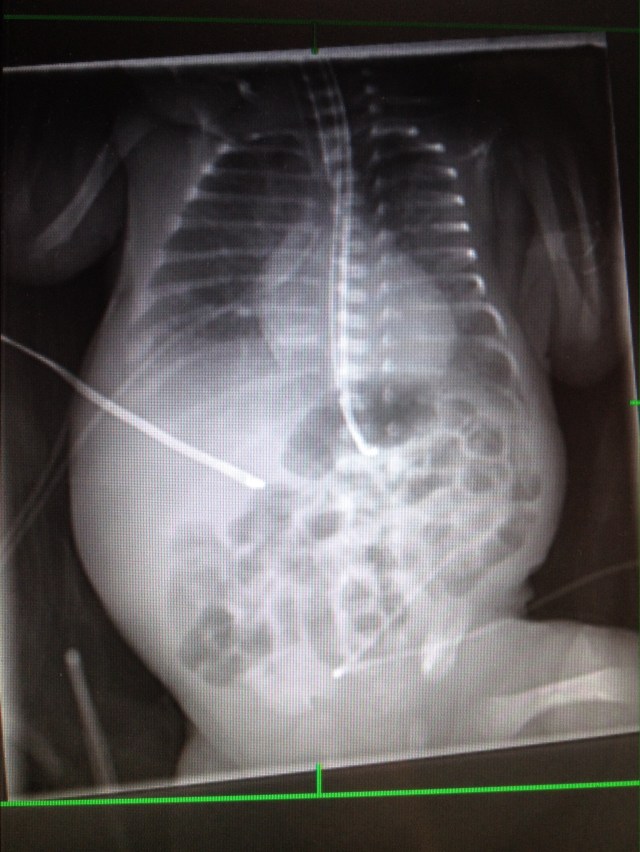

Came in this morning and RT was angry. Super wiggly. Lower lip quivering so probably crying which was the first time I’ve seen this. Noticed he had fluid coming out of feeding tube. Told nurse she sucked out his stomach with syringe. He Has dark fluid in stomach so probably blood+ stomach acid. So likely irritation from medication or tube being in the wrong spot. X-ray is here now to check. Shows proper placement for everything.